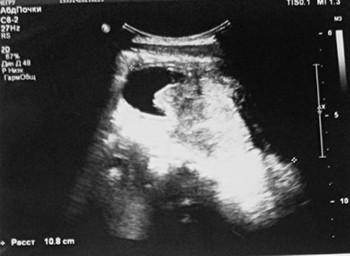

УЗИ почек и надпочечников: УЗ-картина объемного образования мочевого пузыря, забрюшинного пространства (гематома (?) опухоль (?) абсцесс (?)) (см. рис. 2);

Рисунок 2. Результаты УЗИ почек и надпочечников.